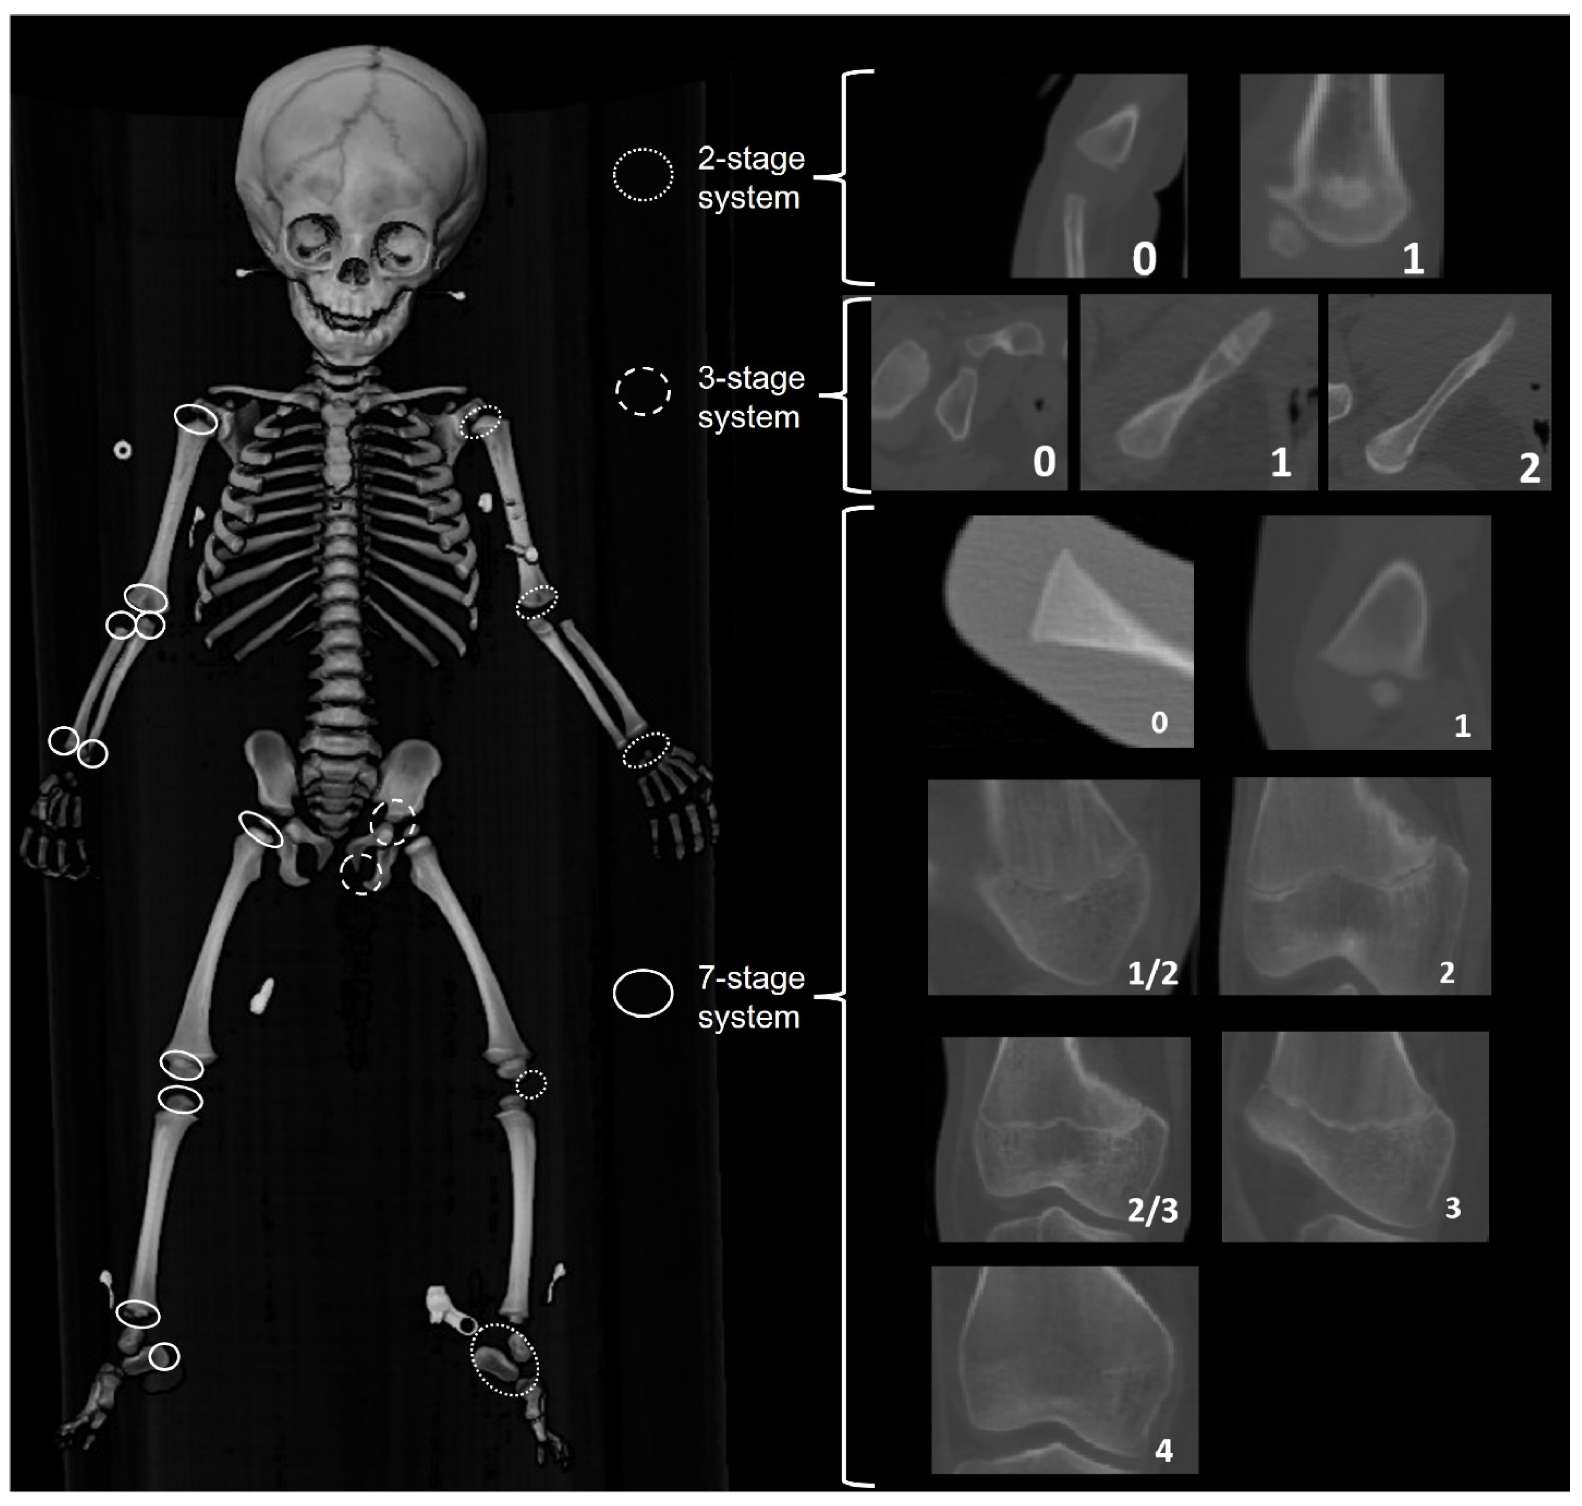

Figure 8.

Three staging systems used to score the ossification of secondary centers, carpals, and tarsals (2-stage system) and epiphyseal fusion of the long bones and pelvis (7-stage system).

2.3.4. Epiphyseal Fusion (EF)

Epiphyseal fusion stages for proximal and distal long bone epiphyses, the calcaneal tuberosity, the ischiopubic ramus, the ilium and ischium, and ossification of the patella were recorded for both left and right-sided elements. Ossification of carpals and tarsals were scored binary absent (0)/present (1), and then the component score was recorded to indicate the number of elements present on either the left or right side. Three different staging systems were employed (Figure 8): a seven-stage system was used for the long bone epiphyses and the calcaneal tuberosity; a three-stage system was used for the pelvic epiphyses; and a binary absent/present was used for the carpals and tarsals, the ossification of the elements of the proximal and distal humerus (e.g., humeral head, lesser tubercle, greater tubercle, capitulum, trochlea, composite epiphyses), and the patella. Epiphyseal fusion was scored on CT slices for France, The Netherlands, Taiwan, and the United States samples, and on radiographs taken for the Angolan, Colombian, and South African samples.